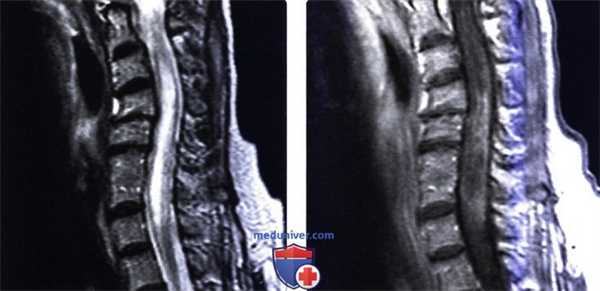

(Слева) Сагиттальный срез, Т2-ВИ: многокамерное кистозное образование, окружающее собой позвонки на уровне среднегрудного отдела позвоночника. Разрушение задней покровной пластинки стало причиной распространения кисты в вентральный отдел эпидурального пространства и сдавления спинного мозга. Твердая мозговая оболочка в подобных случаях обычно остается интактной.

(Справа) Фронтальный срез, Т2-ВИ: эхинококковая киста. Небольшие кисты отделяются от основной кисты, формируя новые кистозные образования. Процесс начинается в теле позвонка и может распространяться на дугу позвонка или смежные ребра.